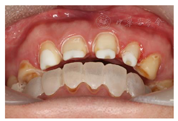

(1)面部检查:面部外形不对称,颏部居中,两侧口角高度不一致,面下1/3高度减小,两侧颧弓突度一致,下颌前突。中位笑线,上唇长度适中(图1)。(2)关节检查:颞颌关节:弹响(-),杂音(-),疼痛(-)。开口度正常,开口型有偏斜,肌肉触诊压痛:右侧上颌结节(+)、左侧上颌结节(++)、双侧翼内肌(+),其他肌肉及颞下颌关节区未诉异常,关节载荷实验无任何紧张和疼痛不适。(3)口内检查:上下颌牙中线较面中线向右偏斜,前后牙广泛不均匀磨耗,前牙磨耗后呈刃状;14、21、22、23及下颌牙唇颊侧颈部见釉质缺损,部分牙本质暴露,呈黄褐色,少量白垩色;44牙见开髓孔,表面暂封。12缺失,缺失牙间隙无。全口牙龈色形质未见异常,11牙、21牙唇侧牙龈龈缘高度不一致,21牙较11牙龈缘高约3mm。全口口腔卫生状况良好,菌斑、软垢少量,未及牙石及牙周袋。咬合检查:11-14牙与对颌牙反

,21牙与31、31牙对刃,左侧尖牙至前磨牙深覆盖,

曲线不平(图2,图3)。(4)影像学检查: